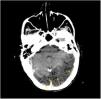

Más datosMujer de 72 años con tos crónica por enfermedad pulmonar intersticial severa y fibrosis. Fue encontrada al despertar en coma, escala de coma de Glasgow 3, desviación de la mirada a la izquierda, hipotonía generalizada, pupilas anisocóricas con midriasis derecha, TC de tórax: pequeño neumotórax apical izquierdo y presencia de aire ectópico en mediastino superior (flechas) (fig. 1), TC cerebral: numerosas burbujas aéreas que se disponen en los surcos cerebrales (flechas), así como áreas hipodensas córtico-subcorticales de distribución parcheadas en áreas parietooccipitales bilaterales (fig. 2). El mecanismo implicado que podría explicar nuestro caso (en ausencia de foramen oval permeable) sería el shunt intrapulmonar. Un aumento brusco de la presión intratorácica por maniobras de Valsalva junto con la producción del neumotórax y el neumomediastino sobre un pulmón patológico podría facilitar el paso de aire a las venas pulmonares y de ahí al sistema circulatorio izquierdo provocando embolismos aéreos en el cerebro.